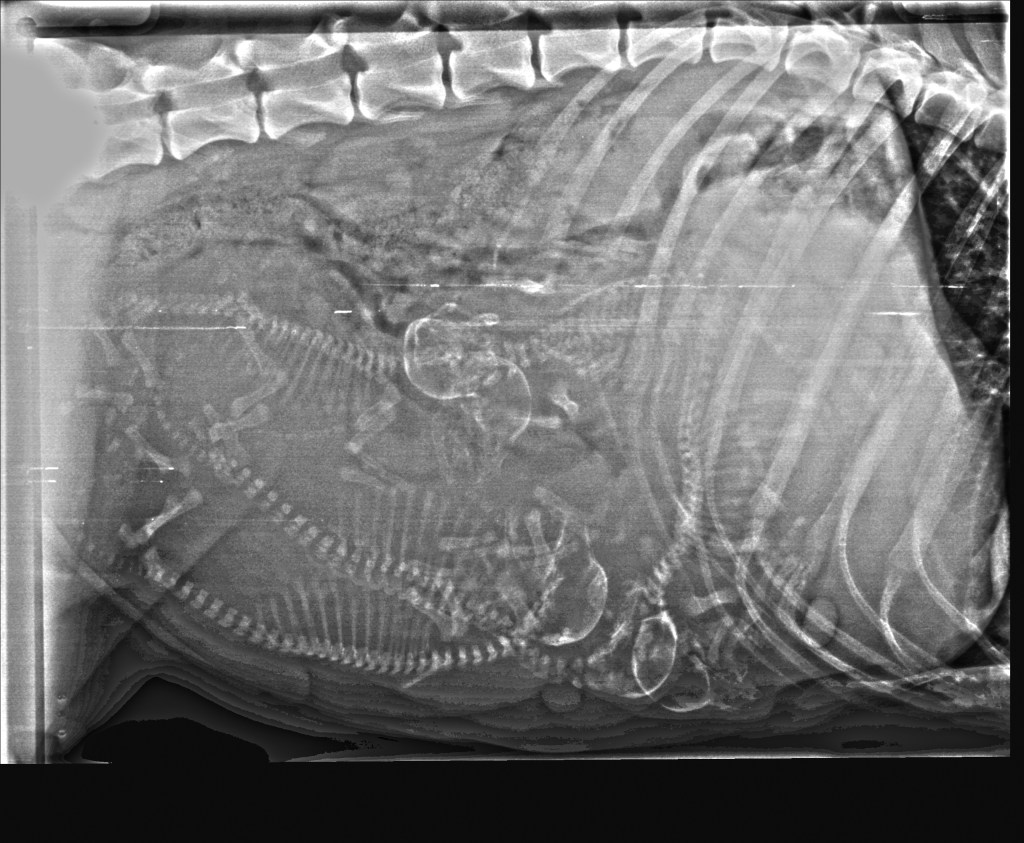

Hvor mange ser du?

Hei! Da har vi vært inne til røntgen av magen til Izel. Hvor mange teller du? Vi så hvertfall 5 hos veterinær. Legger ved både redigert bilde så det skal være enklere å telle i tillegg til original. Trykk på bildene for å se det i større format.